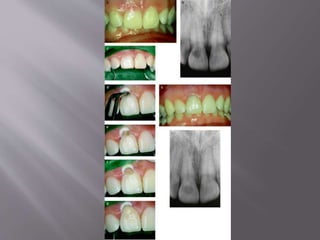

Radiographic view presenting a

process of cervical resorption in the

maxillary right lateral incisor.

Frontal view of maxillary right

lateral incisor 3 years after

treatment of

the adjacent central. Note the

cervical discoloration

 A limited labial flap was raised, revealing a large

resorption lesion with soft tissue growing into the

tooth. The lesion borders included the cementoenamel

junction and down to the cervical part of the root.

Flap elevation of the cervical

lesion. Note the granulation tissue.

After removal of the granulation

tissue.

Orthodontic root extrusion,

onset of movement. After second fiberotomy procedure.

Note exposed gingival lesion

borders

Radiographic view close to end

of movement

Occlusal view of root prepared

for a post and core, leaving

sound dentin treated with TCA

Follow-up at 42 months: clinical

and x-ray examination.